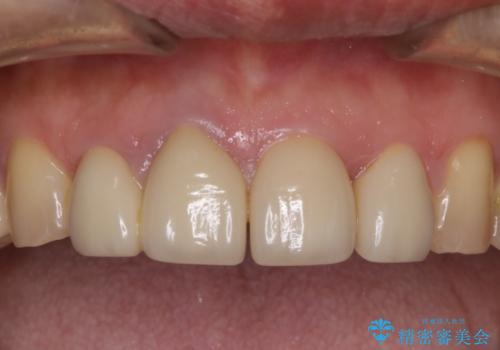

前歯の被せ物をリニューアル

- 上の前歯の正中離開と色味の不満を主訴にご来院されました。

神経を取っている右上2番目の歯は根尖部に病巣があったため根管治療をした上で土台を立て、被せ物の作製を行いました。右上1番目の歯は他院にてとても大きく深い金属の土台が入れられており被せ物の色調に影響を与えていましたが、すべて取りきることのリスクが高いため途中まで除去し目立ちにくいファイバーコアで補強と色調の改善を行いました。